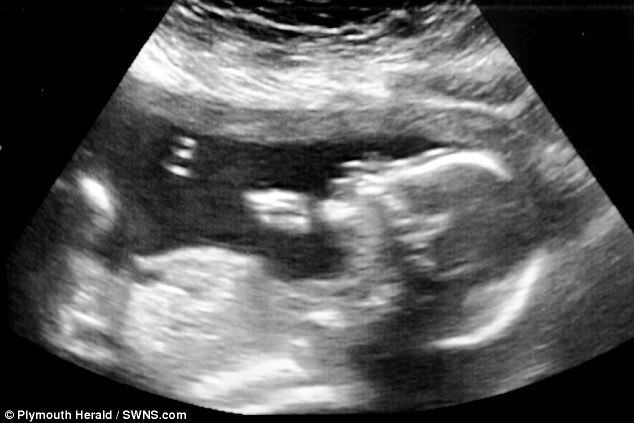

A bebê Frankie Lavis teve um problema raro chamado espinha bífida, diagnosticado quando ainda tinha 20 semanas no útero da mãe. A pequena, hoje com dois anos, foi operada dentro do útero, durante a 24ª semana de gravidez. Desenganada pelos médicos, se...

A bebê Frankie Lavis teve um problema raro chamado espinha bífida, diagnosticado quando ainda tinha 20 semanas no útero da mãe. A pequena, hoje com dois anos, foi operada dentro do útero, durante a 24ª semana de gravidez. Desenganada pelos médicos, seu futuro seria em uma cadeira de rodas, mas a menina já começou a dar os primeiros passos! Conheça mais da história dela, que vive no Reino Unido (Fonte Daily Mail)